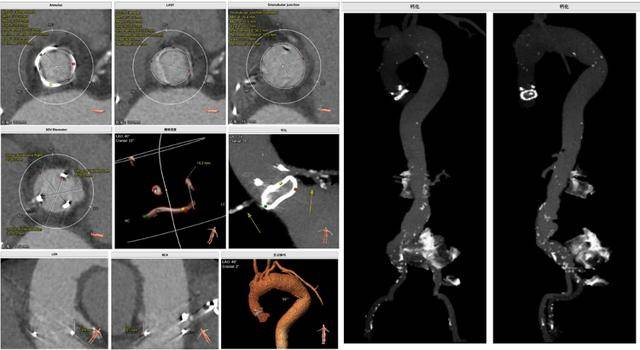

术前CT评估示:

测得外科生物瓣内圈面积413.5mm^2,折合内径22.9mm;测得瓣架高度15.3mm;主动脉弓-降主动脉可见锐折角;主动脉各段-髂总动脉可见散在点状钙化及瘤样扩张;左右冠同窦,窦部空间充足,双侧冠脉风险低。